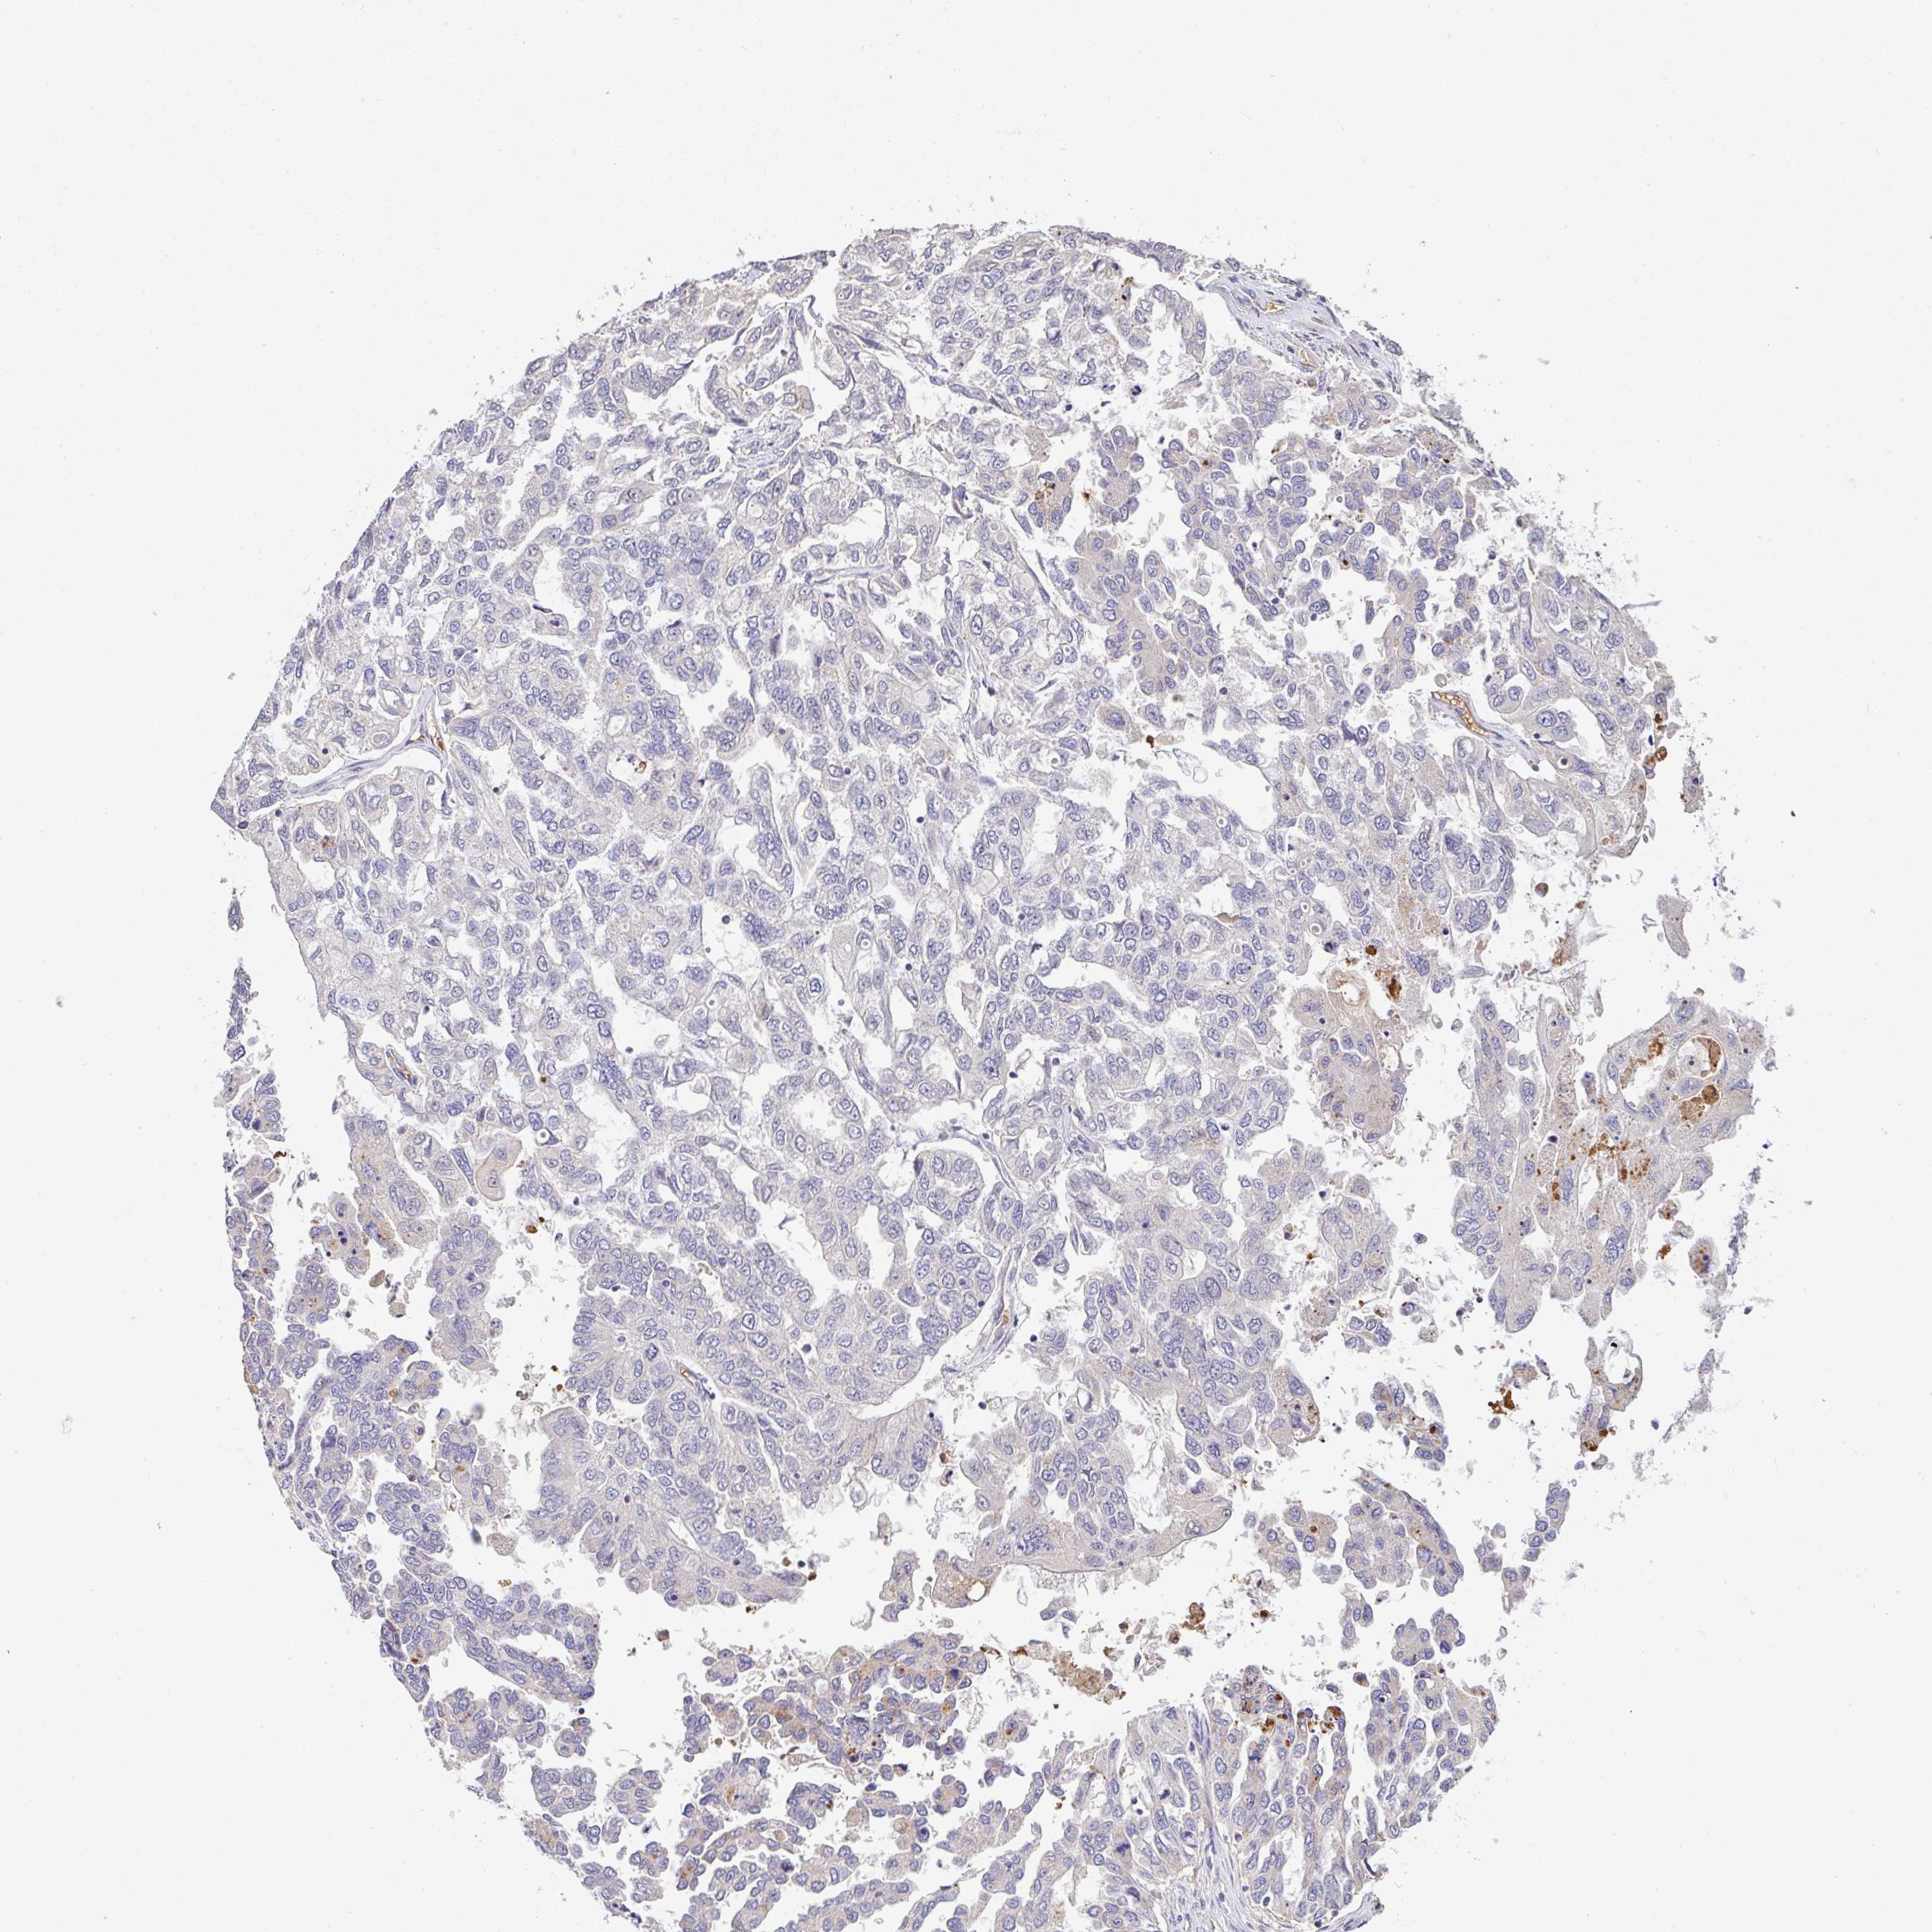

OVARIAN CANCER - Protein expressioni

A mouse-over function shows sample information and annotation data. Click on an image to view it in a full screen mode. Samples can be filtered based on level of antibody staining by selecting one or several of the following categories: high, medium, low and not detected. The assay and annotation is described here.

Note that samples used for immunohistochemistry by the Human Protein Atlas do not correspond to samples in the TCGA dataset.

Antibody stainingi

Antibody staining in the annotated cell types in the current human tissue is reported as not detected, low, medium, or high, based on conventional immunohistochemistry profiling in selected tissues. This score is based on the combination of the staining intensity and fraction of stained cells.

Each image is clickable and will lead to virtual microscopy that enables deeper exploration of all samples and also displays staining intensity scores, fraction scores and subcellular localization as well as patient and tissue information for each sample.

Antibody HPA056632

Cystadenocarcinoma, serous, NOS

Cystadenocarcinoma, mucinous, NOS

Carcinoma, endometroid